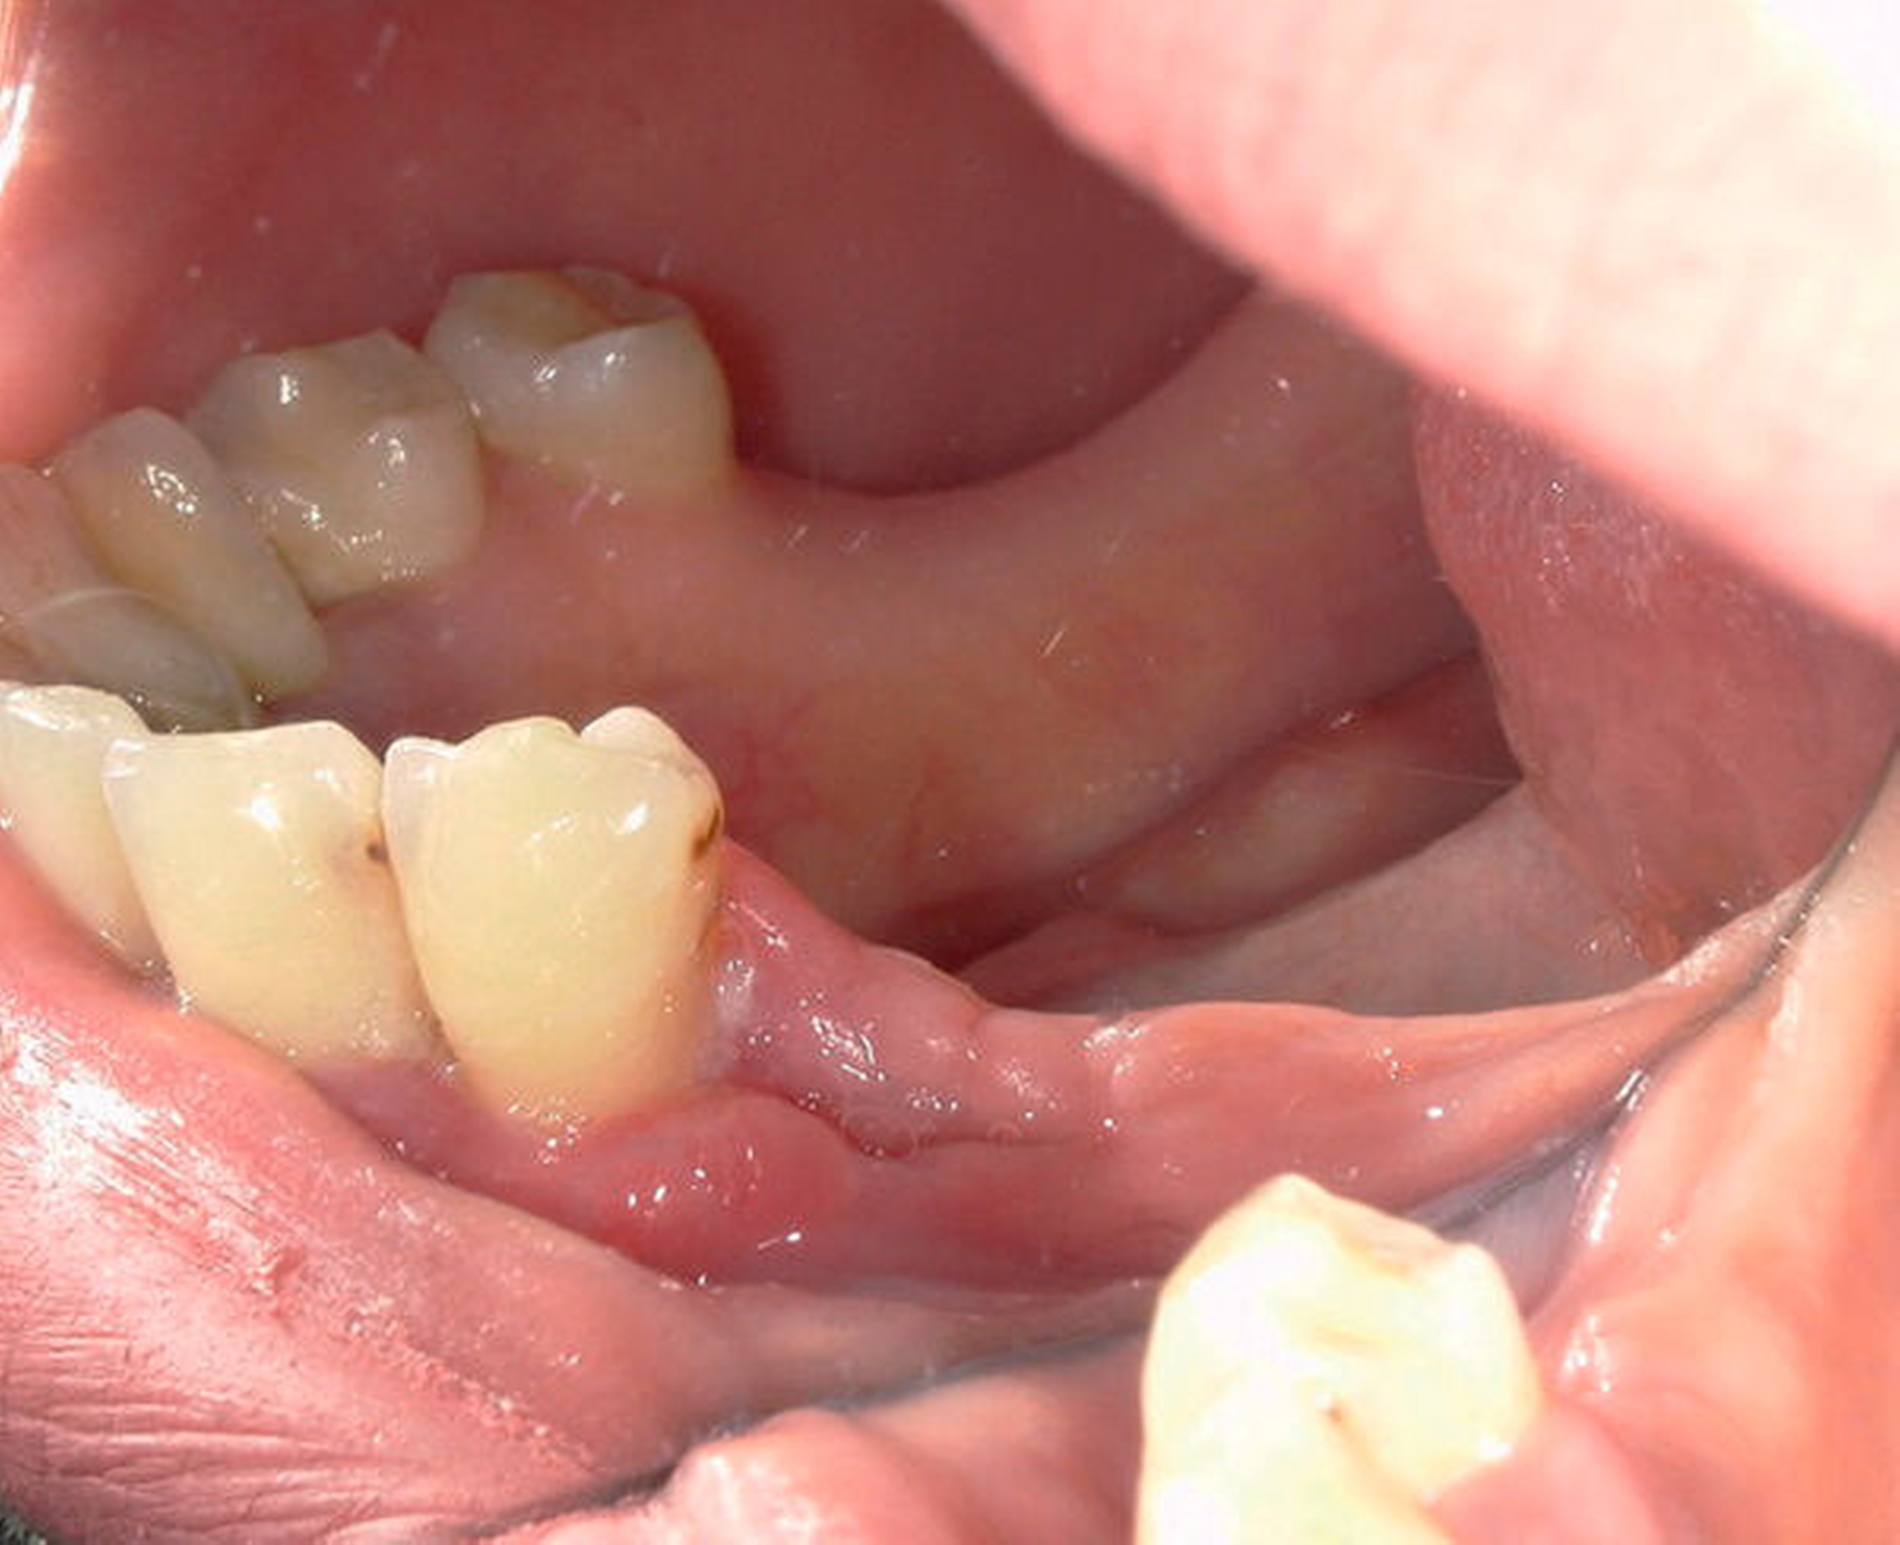

Bei der klinischen Untersuchung zeigte sich eine circa 1 cm messende kugelige Gingivaproliferation regio 34/35 (Abbildung 1). Anamnestisch ergaben sich ein Nikotinkonsum von 7 Packyears (aktuell reduziert) sowie nach Auskunft der Patientin leichte, ziehende Schmerzen in der entsprechenden Region. Die Patientin befand sich zum Zeitpunkt der Vorstellung in der siebten Schwangerschaftswoche. In der Panoramaschichtaufnahme sowie in der Einzelzahnaufnahme zeigte sich eine Abnahme der krestalen Knochenhöhe im Bereich der bereits gelockerten Zähne 34 und 35 (Abbildung 2). Zum Ausschluss eines Malignoms erfolgte noch am selben Tag eine Biopsieentnahme. In der kritischen Wertung der Histologie heißt es: „Akanthotisch verbreitertes Plattenepithel mit unterlagernder Fibrose und teils myxoider Transformation. Einer solchen Verbreiterung des Stratum spinosum kann eine mechanische Irritation zugrunde liegen. Das Resektat weist in diesem Fall eine Unterbrechung des Plattenepithels in ein langstreckiges Ulcus mit gemischtzelligem Entzündungsinfiltrat an seinem Grund auf.“

Substanzdefekte, die durch alle Wandschichten reichen, sind nicht das unmittelbare Ergebnis eines Traumas, sondern entstehen vielmehr durch infektiöse, immunologische oder angiologische Ursachen. Im beschriebenen Fall konnte auf der Basis immunhistochemischer Zusatzuntersuchungen eine chronisch-granulierende Entzündung nachgewiesen werden. Die exophytische Raumforderung zeigte keine Malignitätskriterien und kein weiteres Wachstum nach Biopsieentnahme (Abbildung 3). Aufgrund des erhöhten Narkoserisikos während der Schwangerschaft erfolgte die vollständige Befundexzision ambulant in Lokalanästhesie (Abbildung 4). Bei der chirugischen Resektion des Befunds in toto wurden auch die stark gelockerten Zähne 34 und 35 extrahiert.